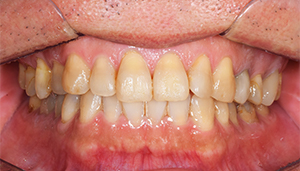

治療前:前の歯

担当医師所見:

前歯部には離開部位があり、歯頚部にはカリエスが認められる。

治療後:前の歯

前歯部はホワイトニング後に、仮歯に置き換え症状のないことを確認してからジルコニアボンドCrにて補綴。 審美性・機能面ともに調和がとれている。